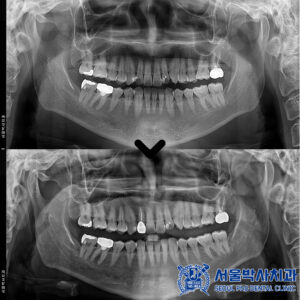

임플란트의 치유 기간이 충분히 지난 뒤,

보철 작업을 진행했습니다.

정밀한 교합과 잇몸 라인을 구현하기 위해

맞춤형 지대주를 제작하고,

이에 맞는 보철물을 장착하였습니다.

또한 주변 인접 치아들도 함께

크라운 보철을 제작하여

전체적으로 기능과 심미성이

조화를 이루도록 마무리했습니다.

마무리 후 사진입니다.